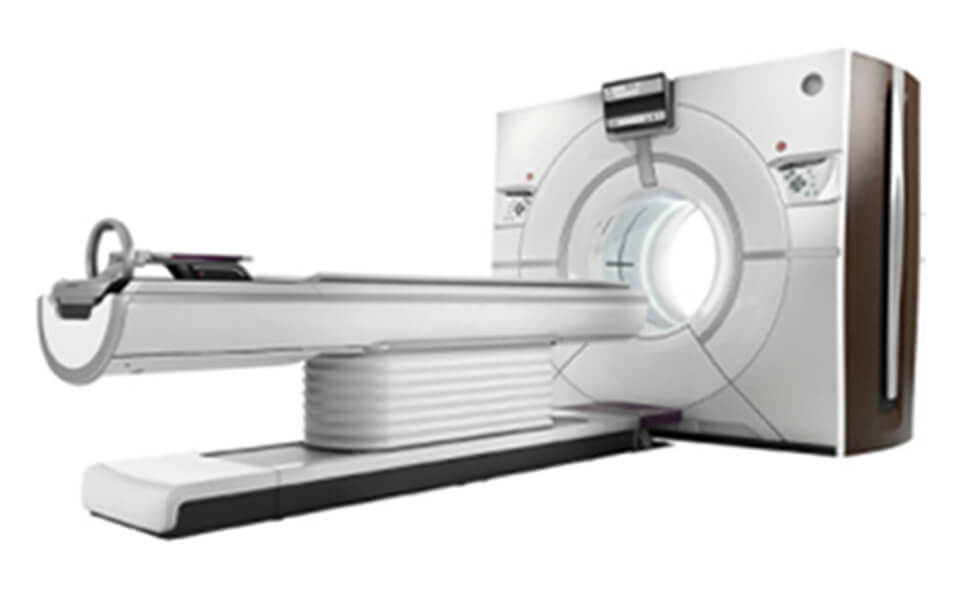

CT部⾨

当センターでは⾼機能CT装置(256列CT、128列CT)計2台が備わっており、広範囲を⾼速に撮影できます。それにより、検査時間が短縮され、患者さんの負担もより少なくなりました。また、Revolution CT(GE社製)は従来装置に⽐べ、造影剤使⽤量の低減、物質の組成を判断する質的診断のサポートも可能となっています。

-

GE社

GE社

Revolution CT(256列) -

SIEMENS社

SIEMENS社

SOMATOM Definition AS+(128列)